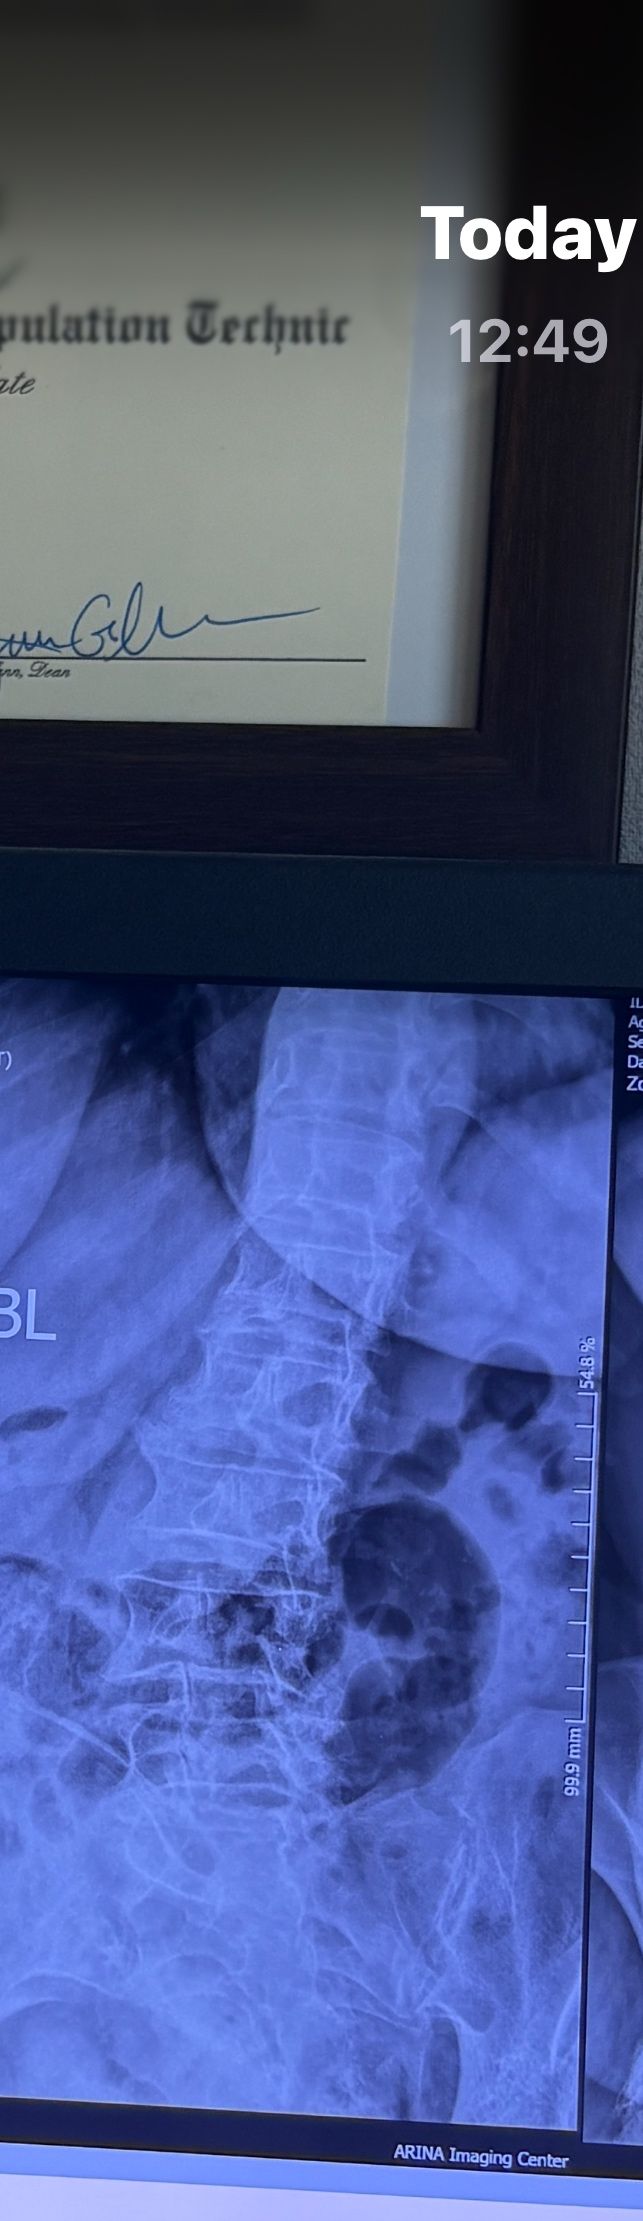

46 years old female patient presented to my clinic yesterday june 1/2025 with LBP and radicular L leg pain for several months which hasn’t responded to physio 2 neurosurgeons have visited her and didn’t suggest any surgery Neurological exam was unremarkable please see her mri/ emg/ncv and her huge tarlov cyst and possible L IVF L4-5 hyperbulge I ordered sacrum mri and ct scan and new emg/ncv and asked her with her sacral Ct scan and MRI first sees another two famous neurosurgeons and see if that large cyst is the reason for her pain if not i can work on her L4-S1 area Do you think her radicular pain can originate from her large cyst in sacrum? Do you consider surgery and removing her sacral cyst?